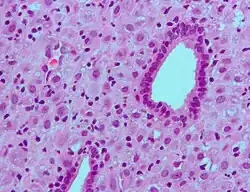

ESC's zijn de bindweefselcellen van het baarmoederslijmvlies die er fibroblastisch uitzien. Decidualisatie zorgt er echter voor dat ze opzwellen en een epitheelcelachtig uiterlijk aannemen als gevolg van de ophoping van glycogeen en lipide druppeltjes. Bovendien beginnen ze cytokinen, groeifactoren en eiwitten zoals IGFBP1 en prolactine uit te scheiden, samen met extracellulaire matrix (ECM) eiwitten zoals fibronectine en laminine. De verhoogde productie van deze ECM-eiwitten verandert het baarmoederslijmvlies in de dichte structuur die bekend staat als de decidua, die stoffen produceert die de aanhechting van trofoblasten bevorderen en een overdreven agressieve invasie remmen.[7]